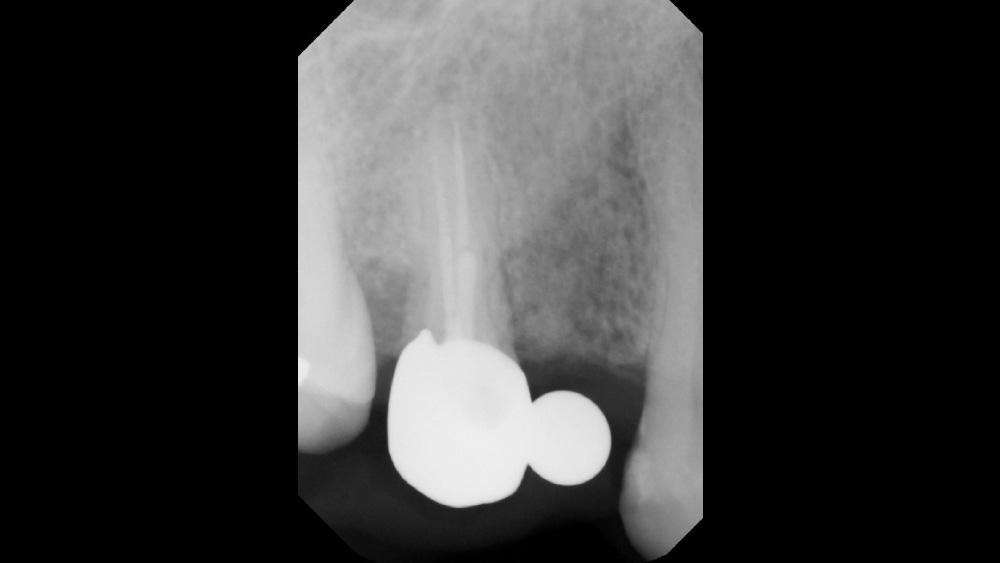

After gaining a clear understanding of the available hard and soft tissue through intraoral evaluation, radiography and — when possible — CBCT scanning, the clinician can determine whether flap reflection or a flapless surgical procedure is ideal for the individual patient. Both of these surgical techniques offer advantages, and the approach should be determined based on the amount of attached tissue present at the implant site, as well as the volume of bone.

The following case, which I performed alongside Dr. Stephanie Tilley of Pensacola, Florida, illustrates the use of both surgical techniques for the same patient, who presented with edentulous spaces in the areas of both right and left maxillary first bicuspids. Due to varying soft-tissue volume on each side of the arch, implant surgery was performed using a flapless procedure for one site, while the attached gingiva was reflected to expose the available hard tissue for the other. As a result of proper site evaluation, treatment planning and restorative-driven implant placement, both surgical techniques led to successful outcomes for the patient.